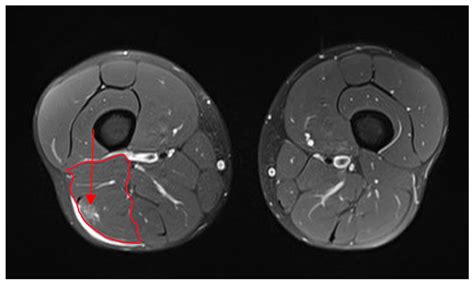

Diagnosing Biceps Femoris Tendinosis

Diagnosing Biceps Femoris Tendinosis involves a combination of physical examination and imaging tests. A healthcare professional will typically:

• Imaging Tests: Order imaging tests such as ultrasound or MRI to visualize the tendon and confirm the diagnosis. These tests can help identify degeneration, thickening, or other abnormalities in the tendon.